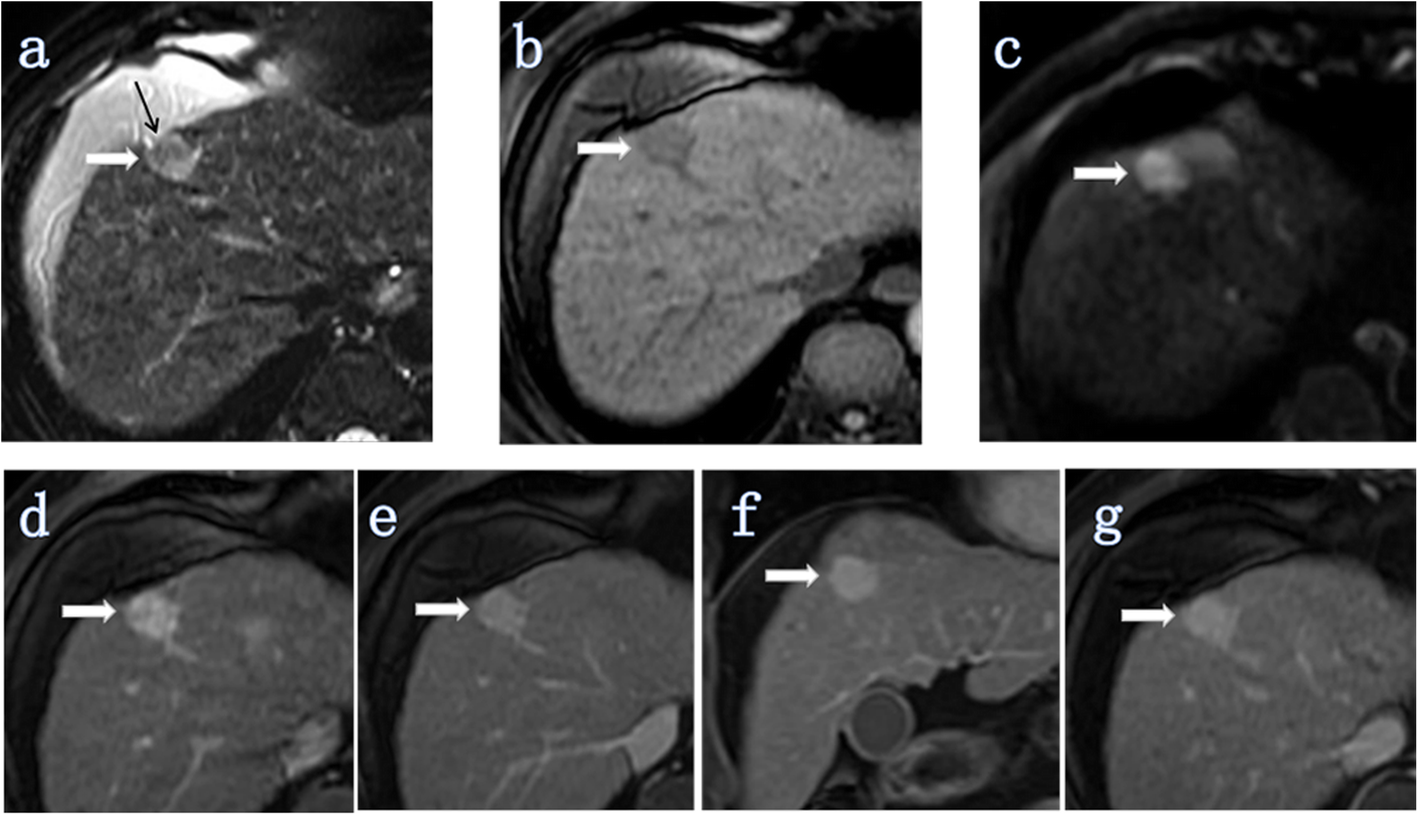

Fig. 5

ICC (white thick arrow) without MVI in a 66-year-old man (tumor grade, G2; CA19–9, < 37 U/ml (20.6 U/ml)). Intrahepatic duct dilatation and visible hepatic artery penetration did not appear in all images of this lesion. a Axial T2-weighted image showing the signal of the tumor was unevenly high intensity and the retraction of the hepatic capsule adjacent to the tumor (black arrow). The tumor morphology was spherical. b Axial T1-weighted-FS image showing that the tumor was located in segment IV of the liver. c Axial DW image (b = 500 s/mm2) showing a uniform high signal. d-g Images during the arterial to delayed phase showing that the tumor showed continuous overall enhancement (high signal). The maximum diameter of the tumor was 1.89 cm and the maximum enhancement edge thickness was 1.89 cm, and the arterial edge enhancement ratio was 100% (1.89/1.89)